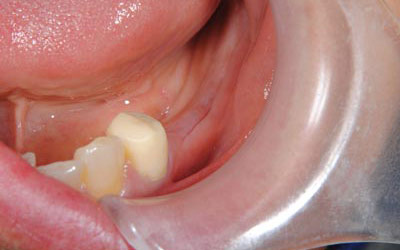

写真は、抜歯後の口腔内の写真です。見るからに、骨が少なく、陥凹してしまっていました。 -